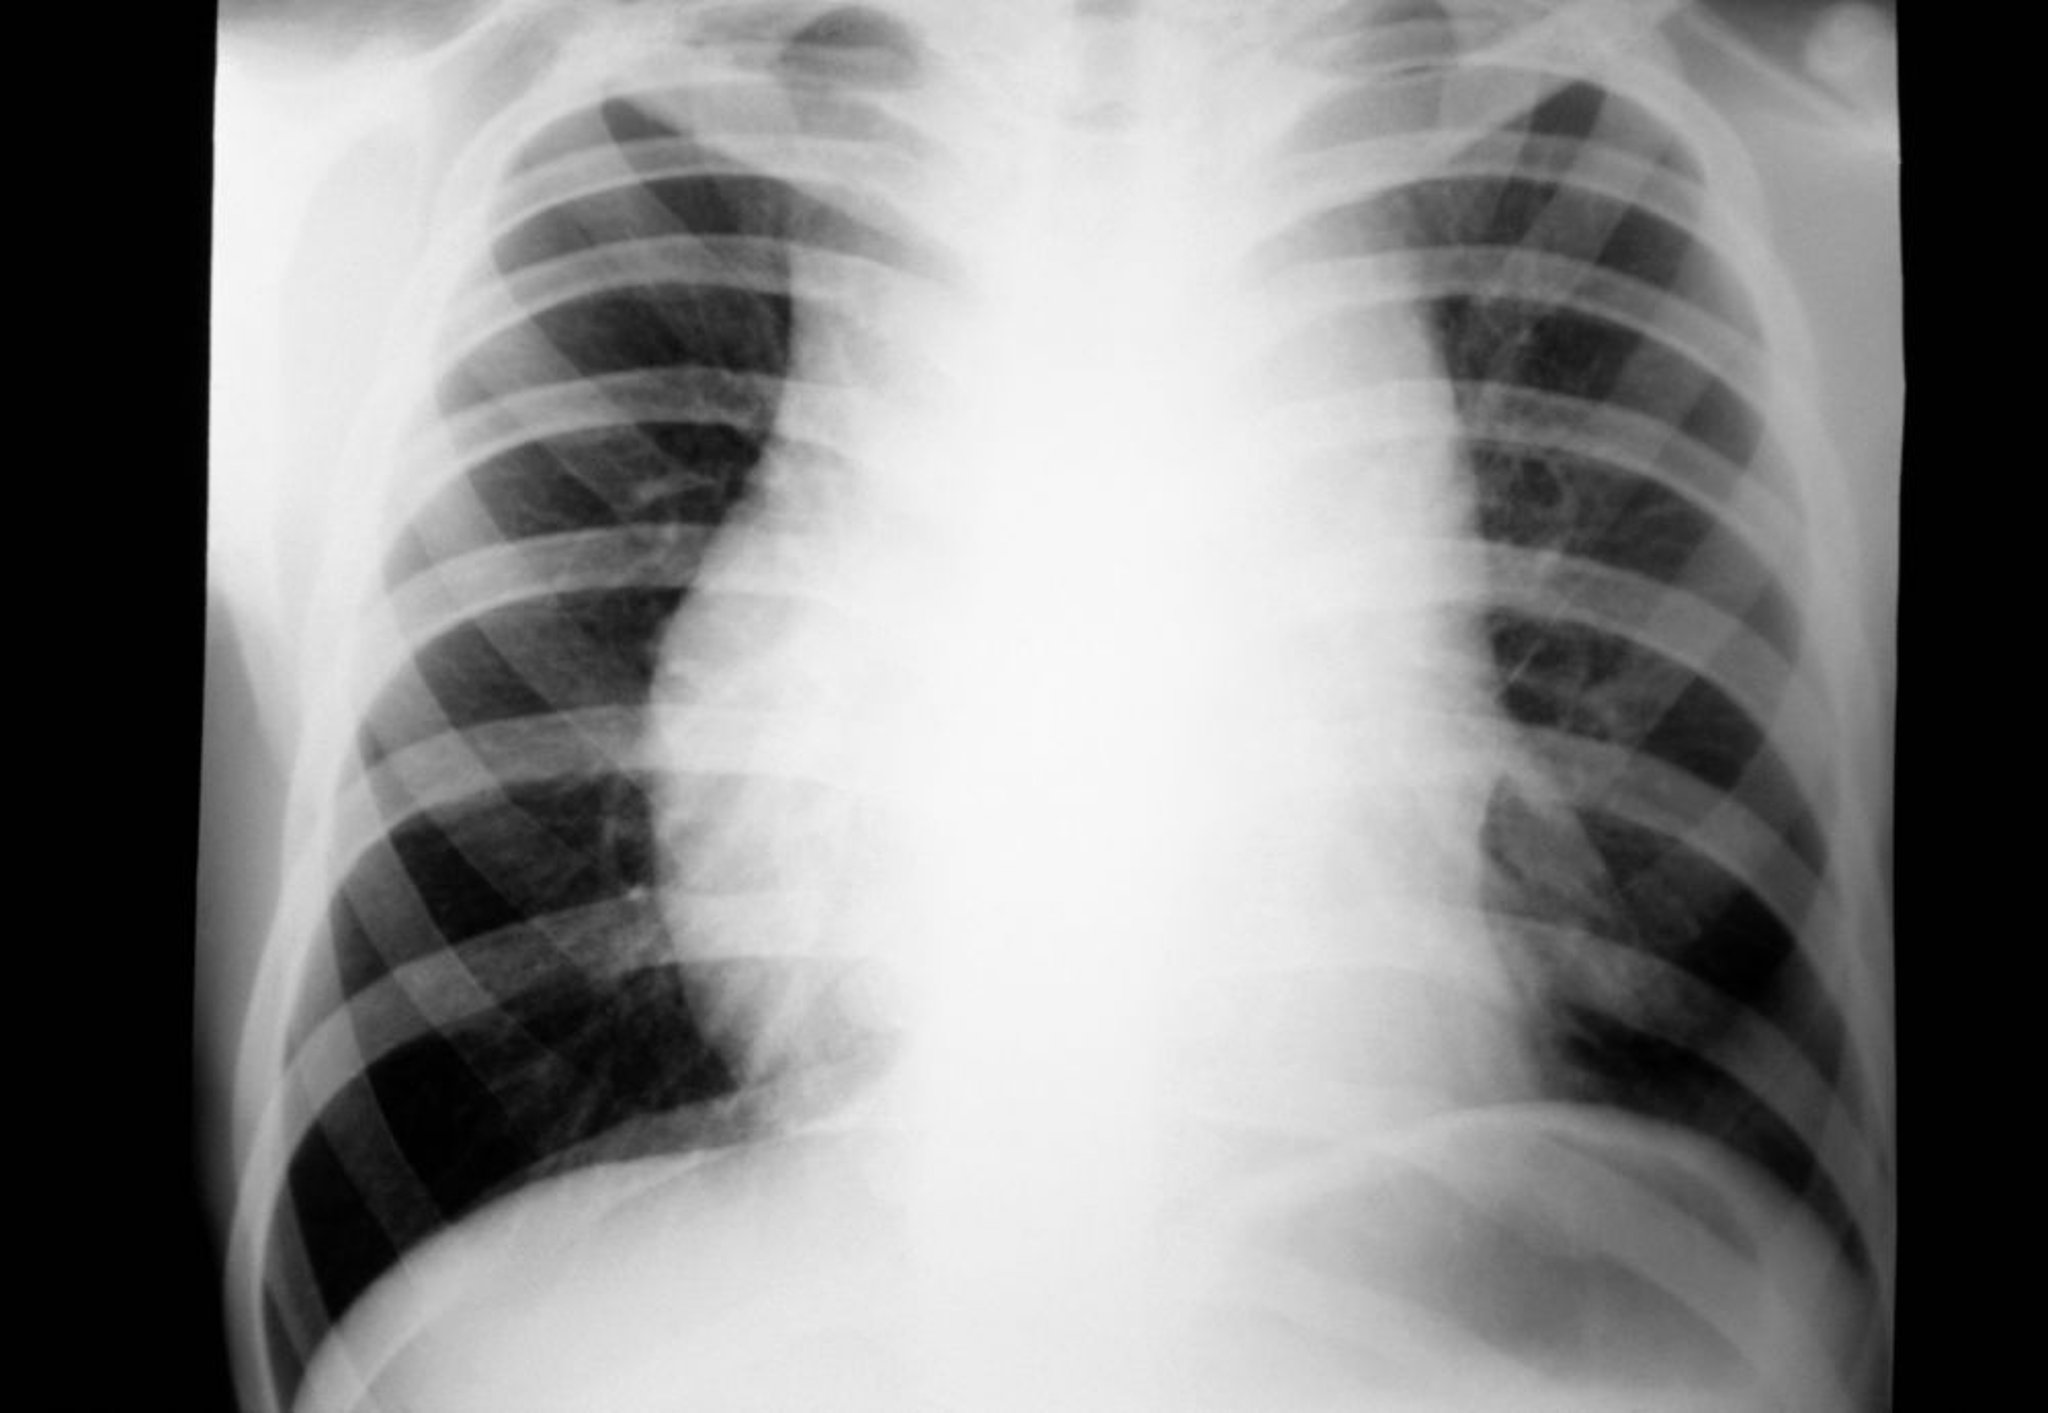

Lymphome de Hodgkin (adénopathie médiastinale)

Radiographie thoracique d'un patient atteint d'un lymphome de Hodgkin montrant une adénopathie médiastinale.